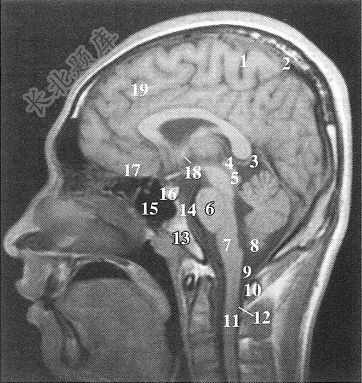

图中标15的解剖结构是()

A、中央旁沟前部

B、距状沟前部

C、蛛网膜下腔

D、大脑镰

E、蝶窦